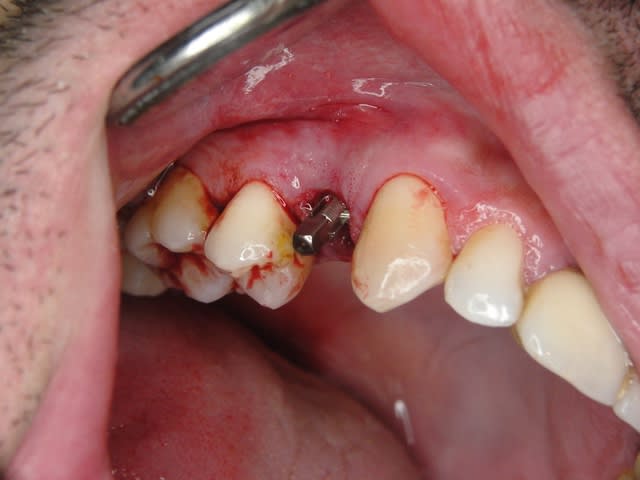

Un patient de 52 ans présente une fracture de racine au site 26.Après division de la racine, extraction de la dent,préparation de la cavité avec un foret conique triangulaire (3 faces,condensation de l´os), puis implantation à 50 Ncm (implant 10mm long, 4,5mm diamètre).Utilisation d´acide hyaluronique pour stimuler la synthèse des ostéoblastes.Pose d´un clip gingival pour préformer la gencive.Après 7 semaines, réalisation d´une empreinte fermée en 5 minutes.Une semaine après, fixation de la couronne définitive ( on observe déjà une ostéointégration).

Bonsoir merci pour ta question, comme tu vois sur la radioDVT il n y avait pas assez de place pour mettre un 6,5mm seulement la racine palatinale était d une longueur de 10/12 mm. Mon premier challenge etait d avoir une premiere stabilité supérieure à 40 Ncm.Le laboratoire est donc important pour que le patient puisse nettoyer facilement la région implantaire.

la radioDVT que j ai oublié de poster